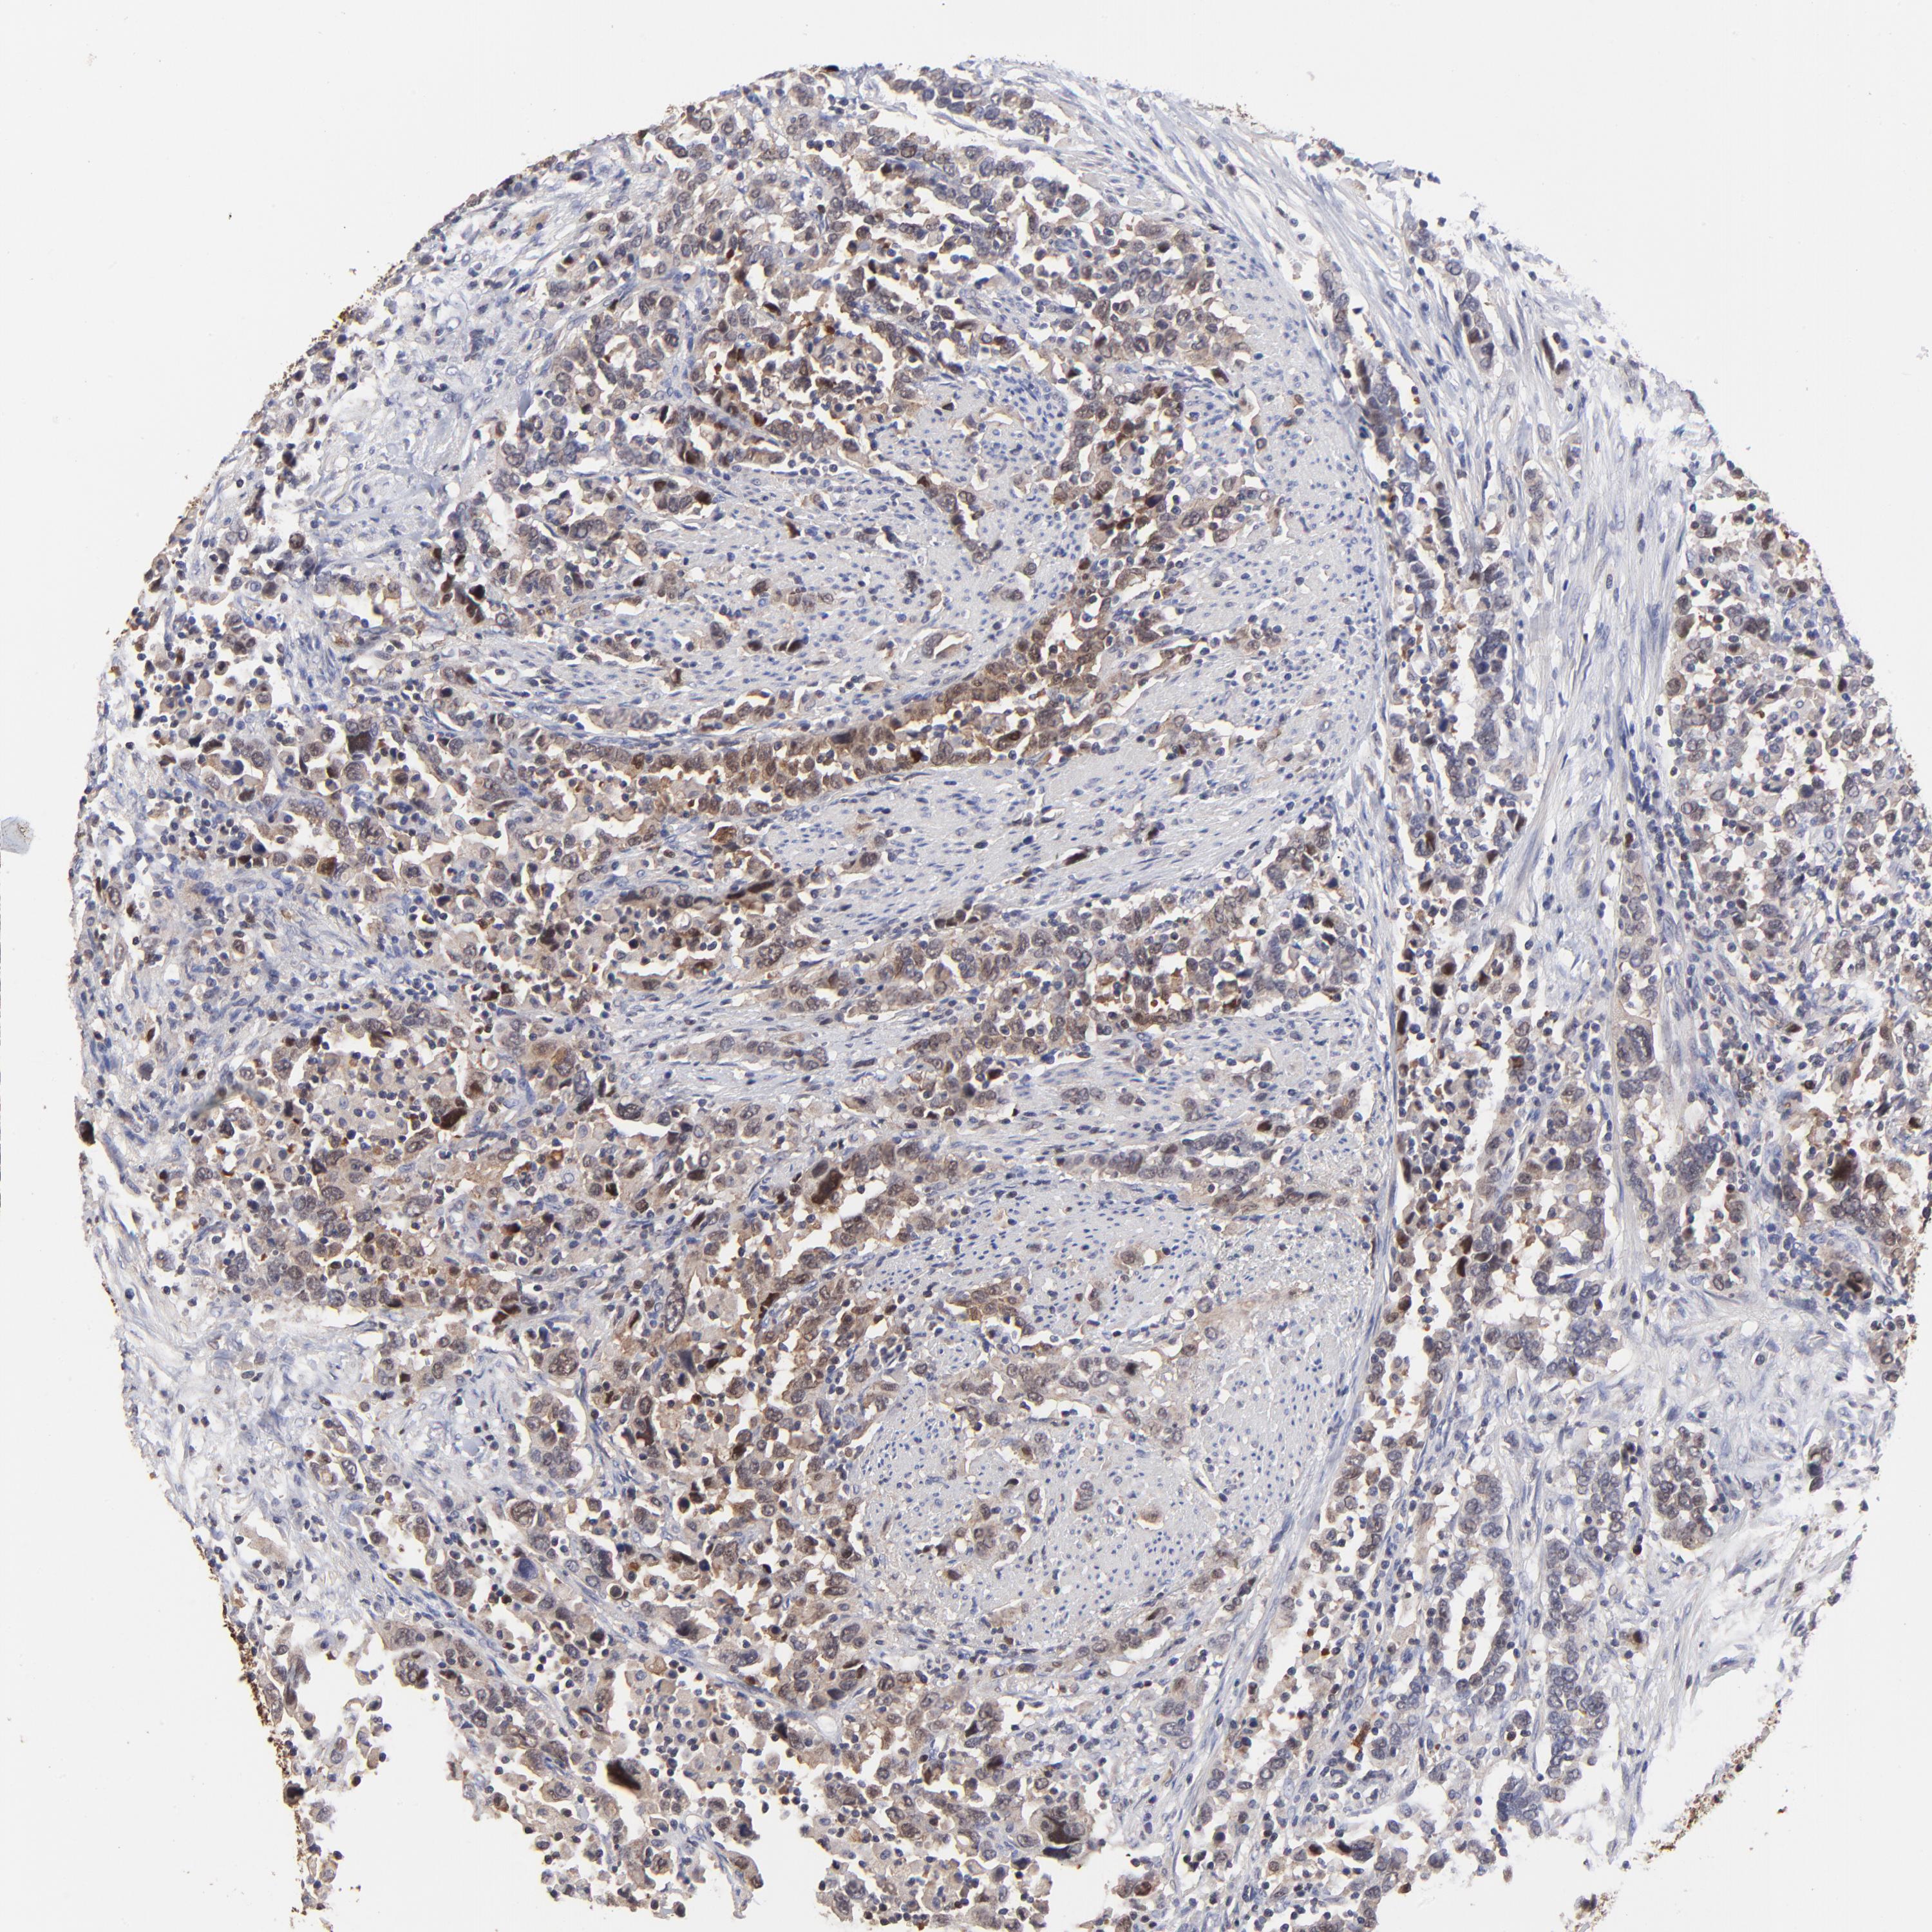

UROTHELIAL CANCER - Protein expressioni

A mouse-over function shows sample information and annotation data. Click on an image to view it in a full screen mode. Samples can be filtered based on level of antibody staining by selecting one or several of the following categories: high, medium, low and not detected. The assay and annotation is described here.

Note that samples used for immunohistochemistry by the Human Protein Atlas do not correspond to samples in the TCGA dataset.

Antibody stainingi

Antibody staining in the annotated cell types in the current human tissue is reported as not detected, low, medium, or high, based on conventional immunohistochemistry profiling in selected tissues. This score is based on the combination of the staining intensity and fraction of stained cells.

Each image is clickable and will lead to virtual microscopy that enables deeper exploration of all samples and also displays staining intensity scores, fraction scores and subcellular localization as well as patient and tissue information for each sample.

Antibody HPA002832

Staining

High

Medium

Low

Not detected

Intensity

Strong

Moderate

Weak

Negative

Quantity

>75%

75%-25%

<25%

None

Location

Nuclear

Cytoplasmic/membranous

Cytoplasmic/membranous,nuclear

Urothelial carcinoma, High grade